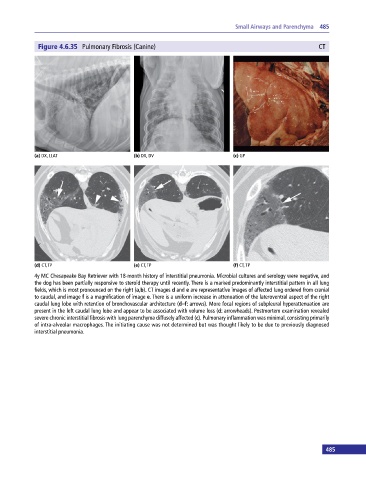

Figure 4.6.35 Pulmonary Fibrosis (Canine) CT

(a) DX, LLAT (b) DX, DV (c) GP

(d) CT, TP (e) CT, TP (f) CT, TP

4y MC Chesapeake Bay Retriever with 18‐month history of interstitial pneumonia. Microbial cultures and serology were negative, and

the dog has been partially responsive to steroid therapy until recently. There is a marked predominantly interstitial pattern in all lung

fields, which is most pronounced on the right (a,b). CT images d and e are representative images of affected lung ordered from cranial

to caudal, and image f is a magnification of image e. There is a uniform increase in attenuation of the lateroventral aspect of the right

caudal lung lobe with retention of bronchovascular architecture (d–f: arrows). More focal regions of subpleural hyperattenuation are

present in the left caudal lung lobe and appear to be associated with volume loss (d: arrowheads). Postmortem examination revealed

severe chronic interstitial fibrosis with lung parenchyma diffusely affected (c). Pulmonary inflammation was minimal, consisting primarily

of intra‐alveolar macrophages. The initiating cause was not determined but was thought likely to be due to previously diagnosed

interstitial pneumonia.